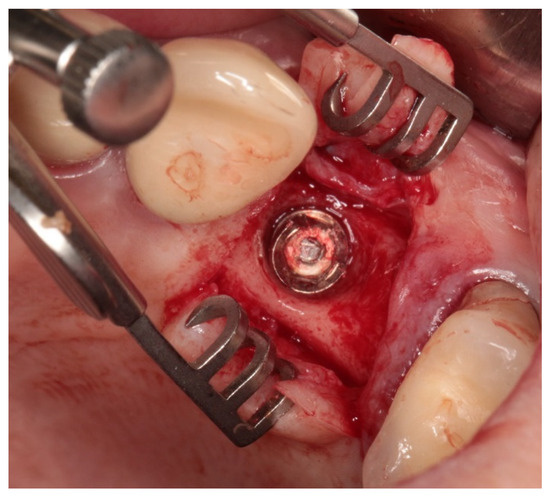

| 7 | lateral | bridge 3 pts. 44–46 | IRES 3.75 mm × 11.5 mm IRES 3.75 mm × 10 mm | The screw tested comes from a 3-point bridge in the lateral section 44–46 mounted on two implants. Implants in the area of the mandibular first premolar (44) with a diameter of 3.75 mm and a length of 11.5 mm. And the second one in the area of the first molar of the mandible, right side (46), with a diameter of 3.75 and a length of 10 mm were implanted in 2018. The prosthetic work was installed in 2019. The tested screw functioned for four years. The patient did not come for regular check-ups, and the screws did not loosen earlier. The examination revealed, in addition to the loose screw, a fracture of the implant 46. |

| 8 | lateral | single crown 24 | IRES 4.1 mm × 11.5 mm | The tested screw was used to attach a single crown to the implant in the area of the maxillary first premolar, left side (24), lateral section. Implant with a diameter of 4.1 mm and a length of 11.5 mm was implanted in 2019. The crown was installed in 2021. The screw worked for two years. The patient came for follow-up visits and the screw was tightened once. |